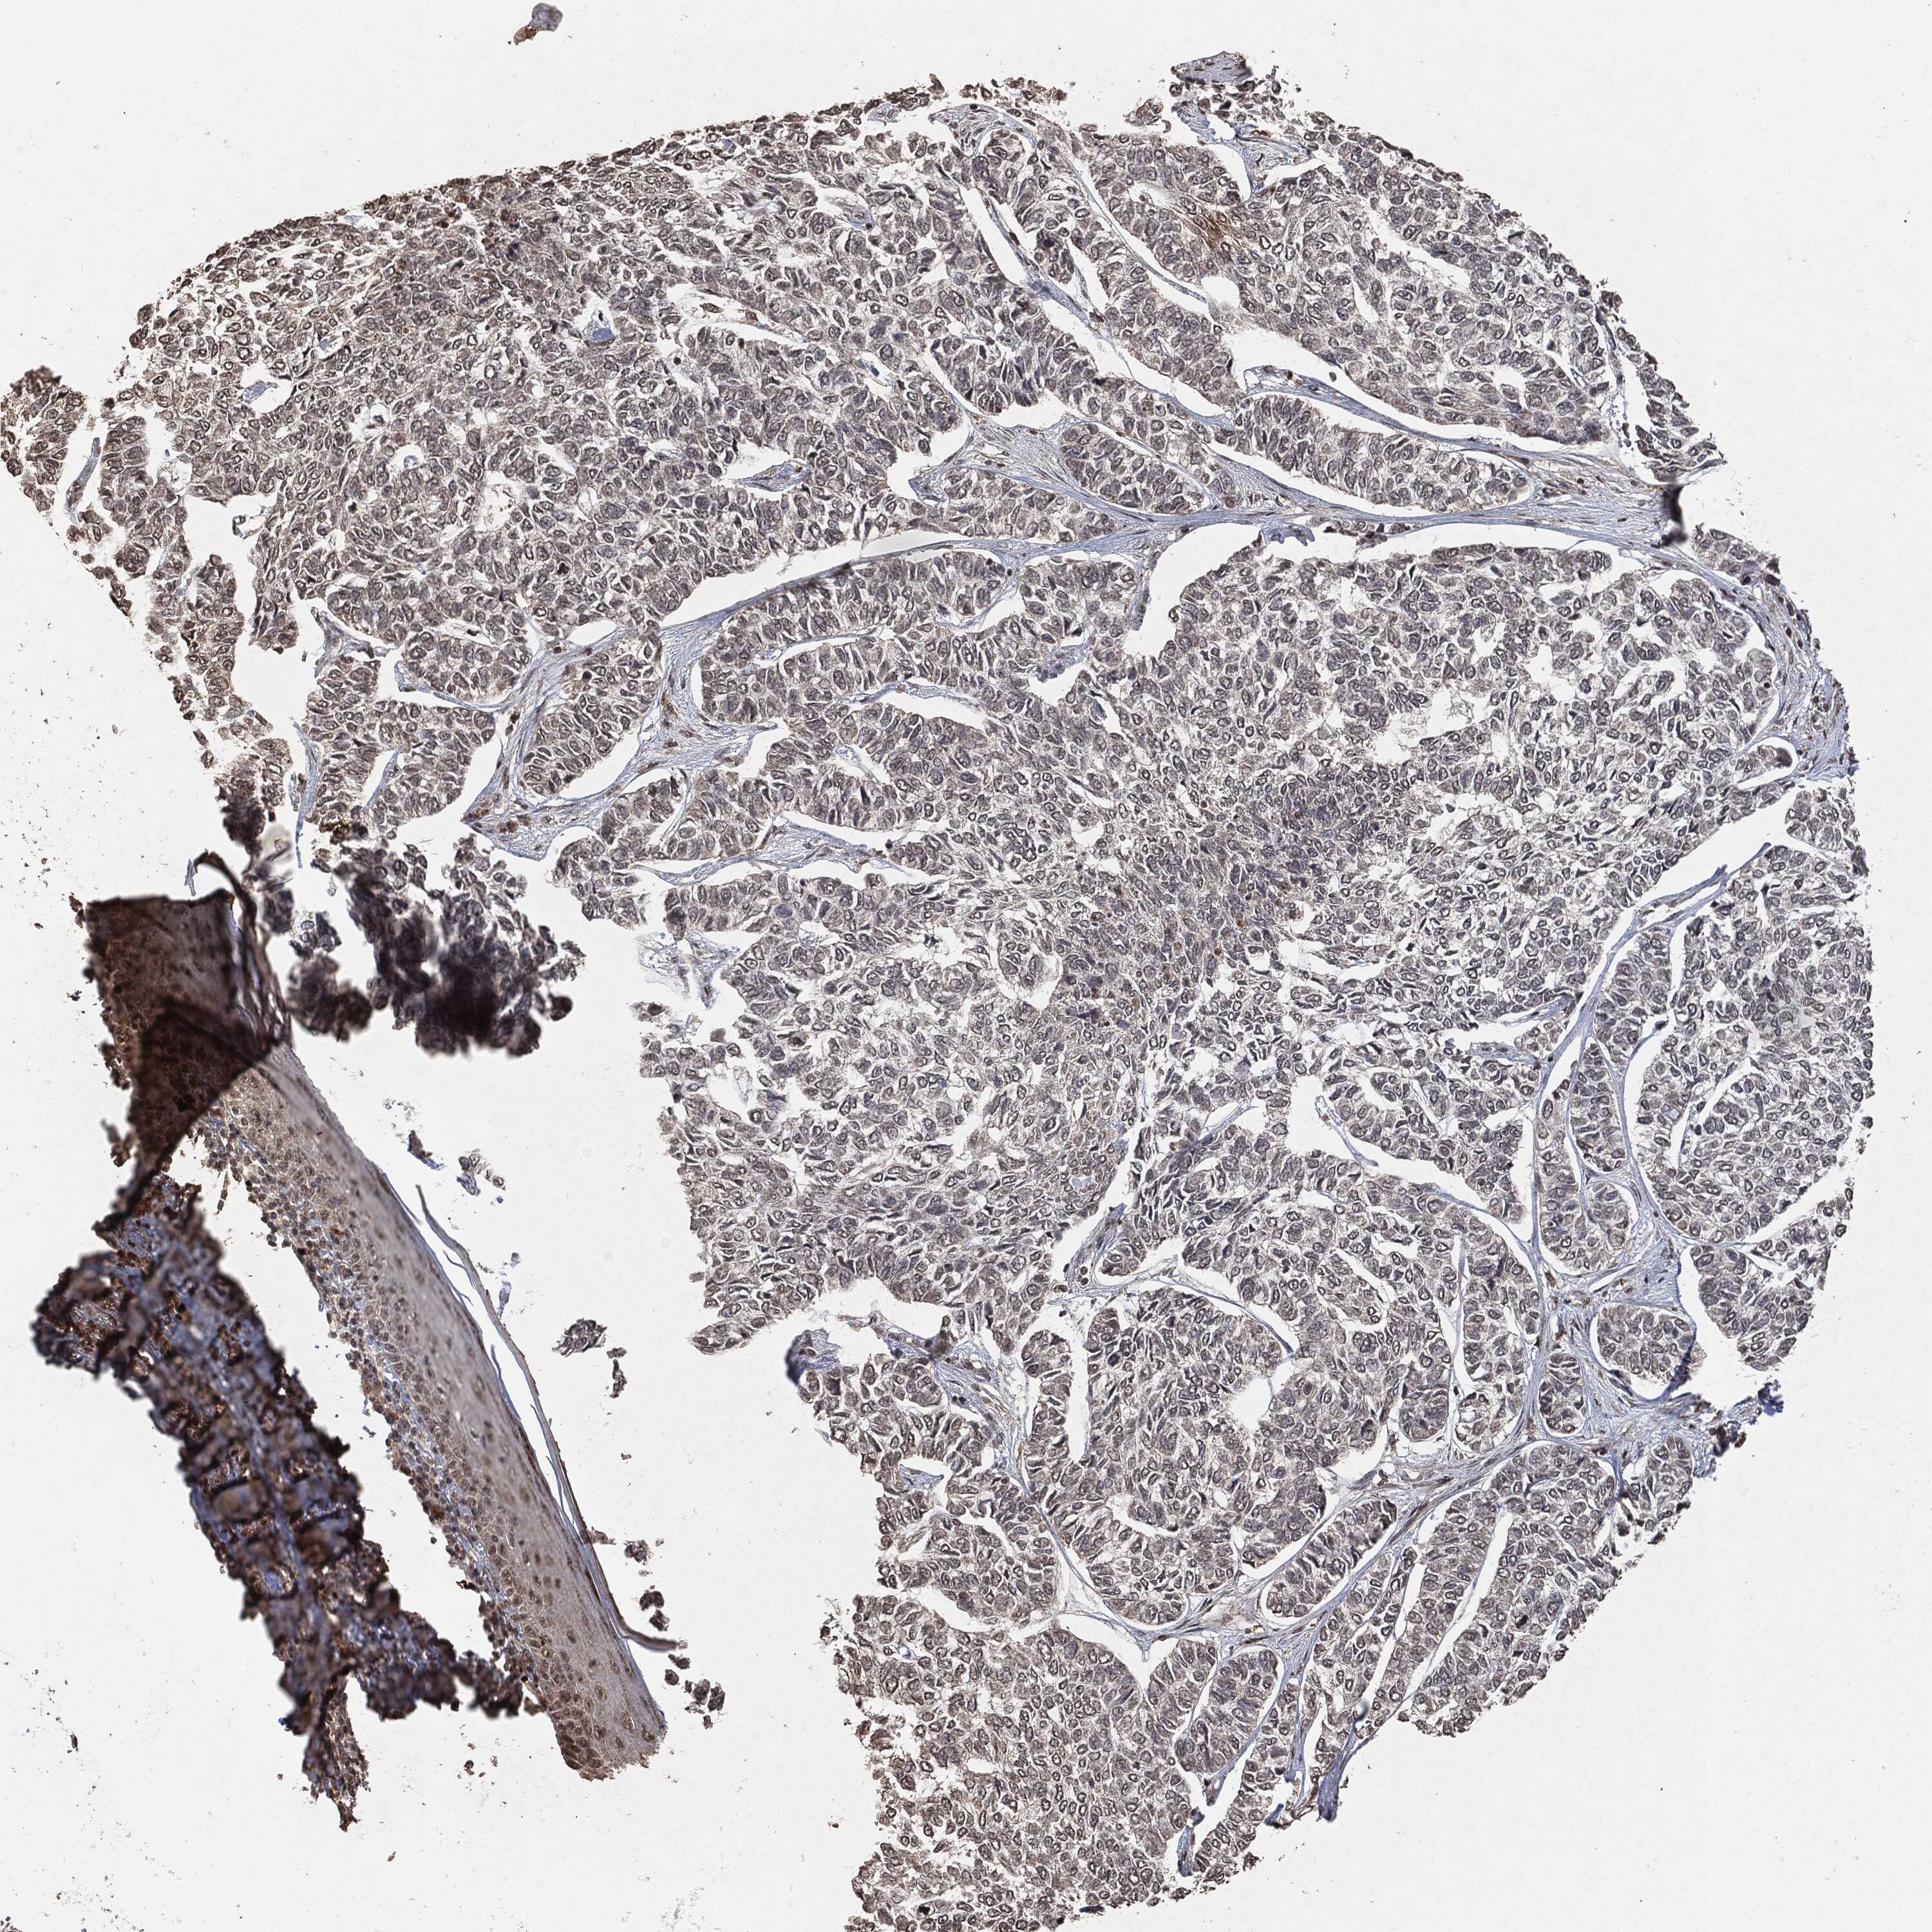

SKIN CANCER - Protein expressioni

A mouse-over function shows sample information and annotation data. Click on an image to view it in a full screen mode. Samples can be filtered based on level of antibody staining by selecting one or several of the following categories: high, medium, low and not detected. The assay and annotation is described here.

Antibody stainingi

Antibody staining in the annotated cell types in the current human tissue is reported as not detected, low, medium, or high, based on conventional immunohistochemistry profiling in selected tissues. This score is based on the combination of the staining intensity and fraction of stained cells.

Each image is clickable and will lead to virtual microscopy that enables deeper exploration of all samples and also displays staining intensity scores, fraction scores and subcellular localization as well as patient and tissue information for each sample.

Squamous cell carcinoma, NOS